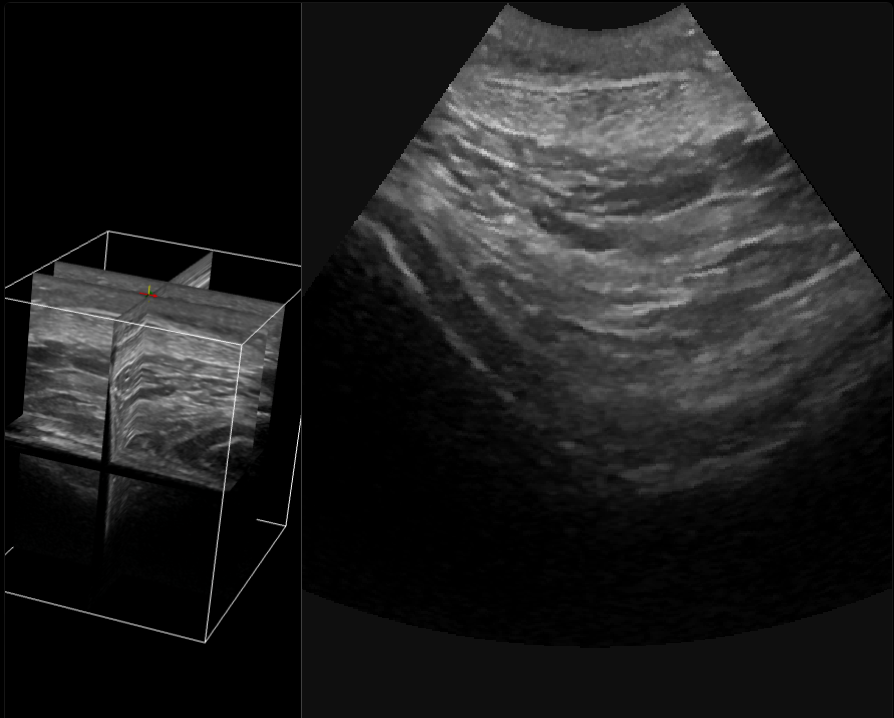

Angulo de insoniación

👉📟 Ir a Imagineus®.

Interacción Sonido con tejidos: Just do It!

Imagenus 1: Ejemplo de imagen ecográfica mostrando estructuras hiper, hipo e isoecogénicas (calota craneal hueso, grasa, lipoma)

👉 Al pulsar sobre la imagen accederás a un jugable docente.